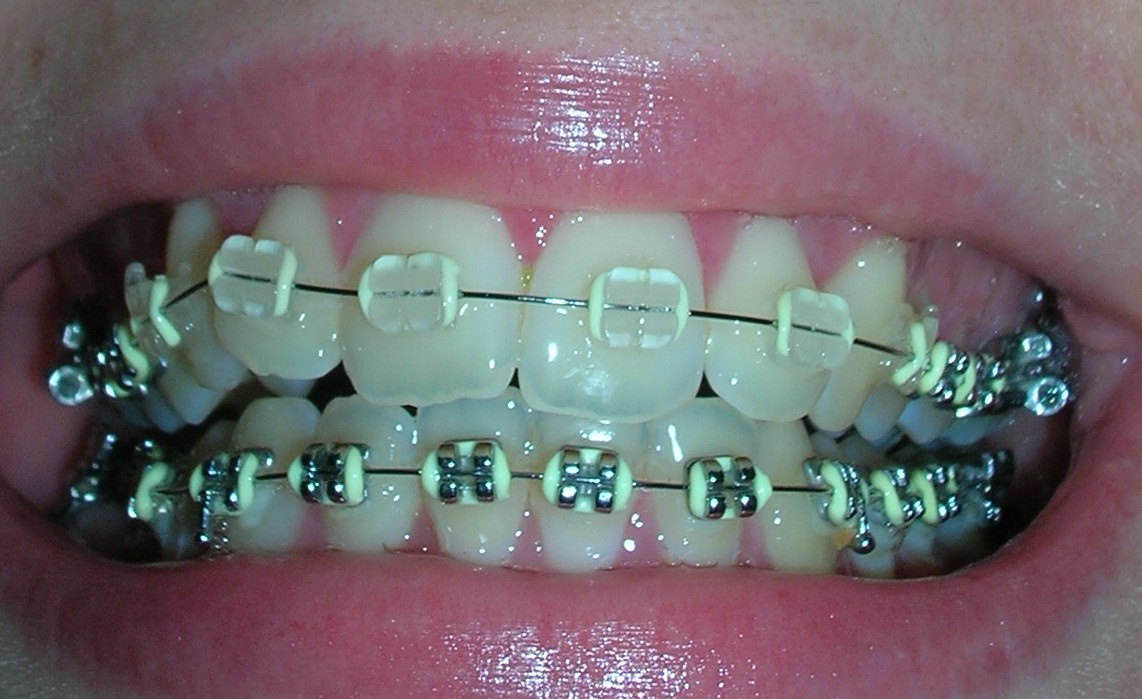

Gek genoeg kan alleen boven keramische brackets (die witte slotjes) en onder niet?! Ik weet eigenlijk niet waarom, maar lijkt me wel apart...Iemand ervaring mee?

Ik heb nog eens gevraagd waarom ik onder geen witte slotjes mag. Vanwege de overbeet zou ik die dan kapot bijten. Of nee, dan bijt je je tandglazuur kapot. Oke, dan maar geen witte slotjes. Onder zie je inderdaad niet zo heel erg...Hij stelde voor om boven 6 witte slotjes te doen, dus alleen dat gedeelte wat zichtbaar is als je lacht/praat. Opzich prima, dat scheelt toch weer geld. (11,50 per bracket extra! :o)

Ja ik heb mn best gedaan voor een duidelijke foto, blijkbaar is dat wel gelukt ;-) Dank voor het compliment hoor..De doorzichtige slotjes zijn mooi, maar ik mocht ze niet onder. Nouja, hij wilde het niet omdat ik ze door de overbeet kapot kon bijten. Hij vind dat ze minder sterk zijn dan de gewone slotjes. Plus het risico dat je je tandglazuur aantast. Ik had alles wit wel mooi gevonden, maar ja, zo kan het ook wel. Je ziet er niet echt veel van als ik praat gelukkig.

En de reacties zijn wel leuk. Zodra ik lach zien mensen het en dan is het "he je hebt een beugel!" Wel grappig..Boven valt een stuk minder op, onder natuurlijk wel omdat die gewoon zijn. Toch vind ik die keramische brackets veel prettiger!